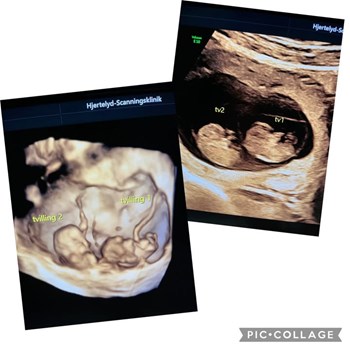

Se hele opslaget på AutoFit A/S’ Facebookside2 små enæggede tvillinger 👶👶 Billeder er taget i uge 8+5 i både 2D og 3D Fostrene er 31 og 33 mm. Når du venter enæggede tvillinger, følges graviditeten ret tæt. Man skal forvente scanning hver 14...